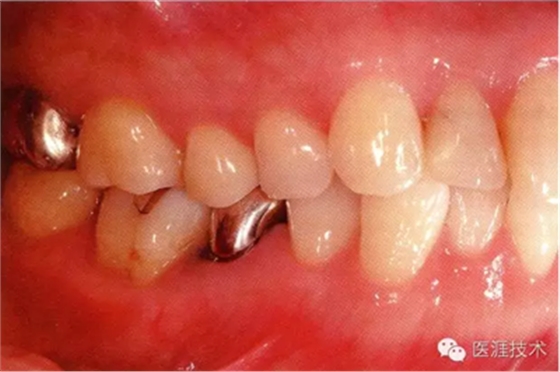

44歲牙周炎女性的臨床照片

44歲患有糖尿病病史(未治愈)。菌斑控制不良。通過牙周探診,全頜有4~8mm的牙周袋,在X光片中可以看到上頜前牙處中度牙槽骨吸收,磨牙處重度牙槽骨吸收。二次齲齒和根面齲齒也有發(fā)生??梢钥吹礁∧[性腫脹,收到刺激后會出血。